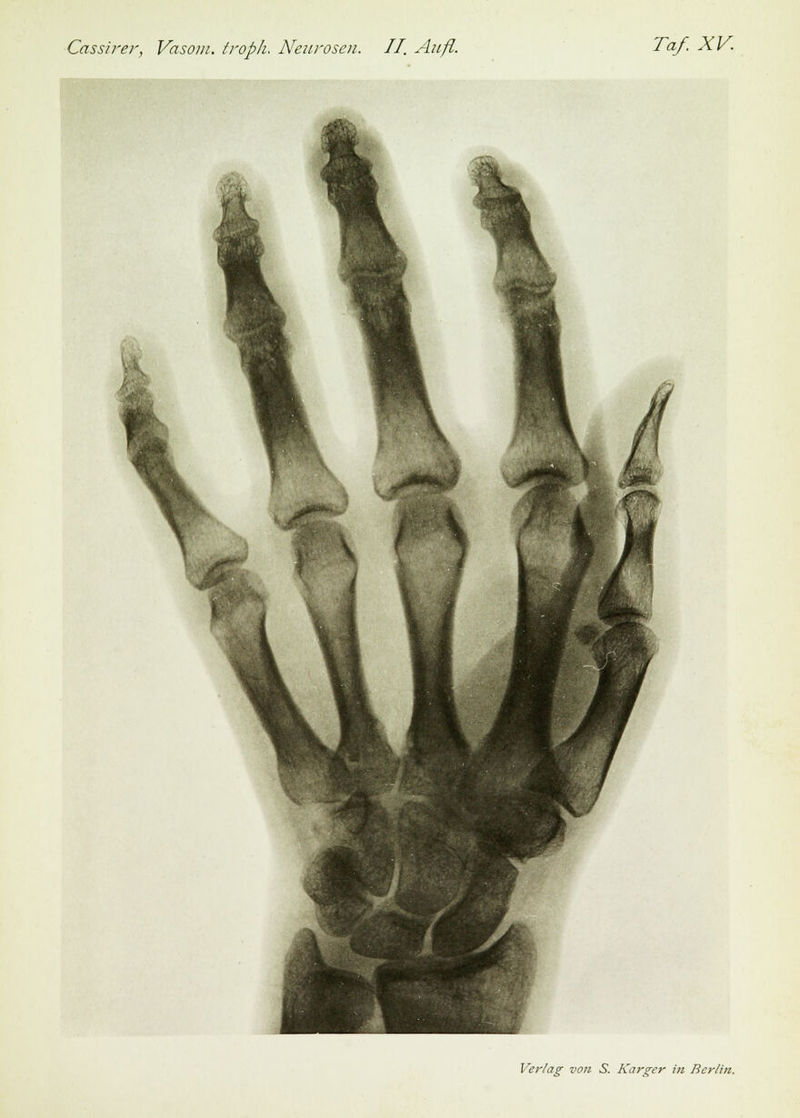

Die vasomotorisch-trophischen Neurosen : eine Monographie / von R. Cassirer.

- Cassirer, Richard, 1868-1925.

- 1912